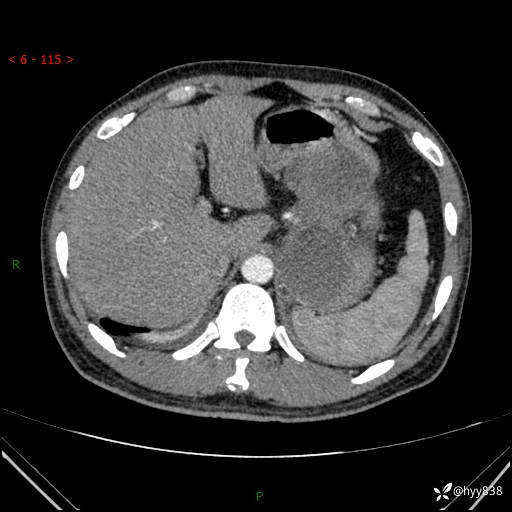

病例39岁/女,左侧腰痛入院。腹腔囊实性肿块,定位、定性---结果公布~

性别:男

年龄:39岁

简要病史:左侧腰痛待查,CT发现腹腔占位

腹部CT平扫+增强